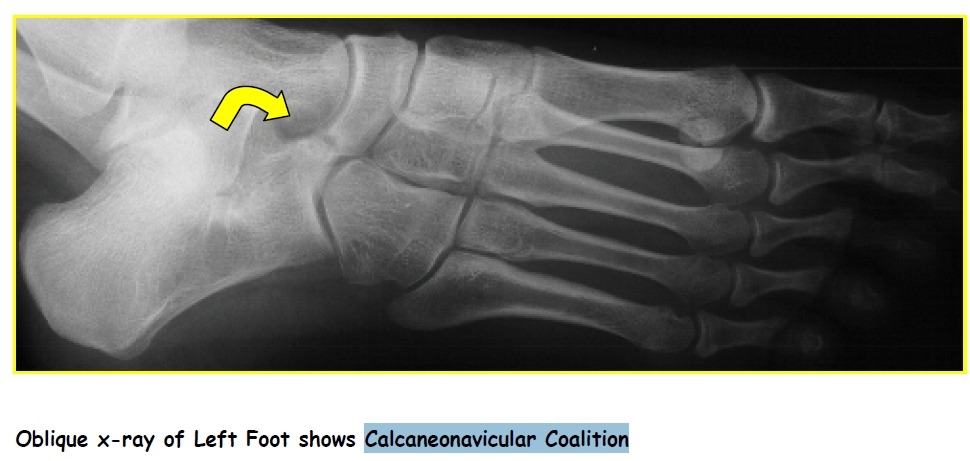

Figure 19 Coalition.

(A) Calcaneonavicular coalition. Lateral view of the ankle shows a talar beak (arrow), which is often

associated with coalition. Note the “anteater sign,” in which the anterior calcaneal process (arrowheads) continues into

the navicular bone, caused by a coalition.

(B) Calcaneonavicular coalition. Lateral oblique view of the foot of the same patient as (A) optimally depicts the site of calcaneonavicular coalition (arrows).